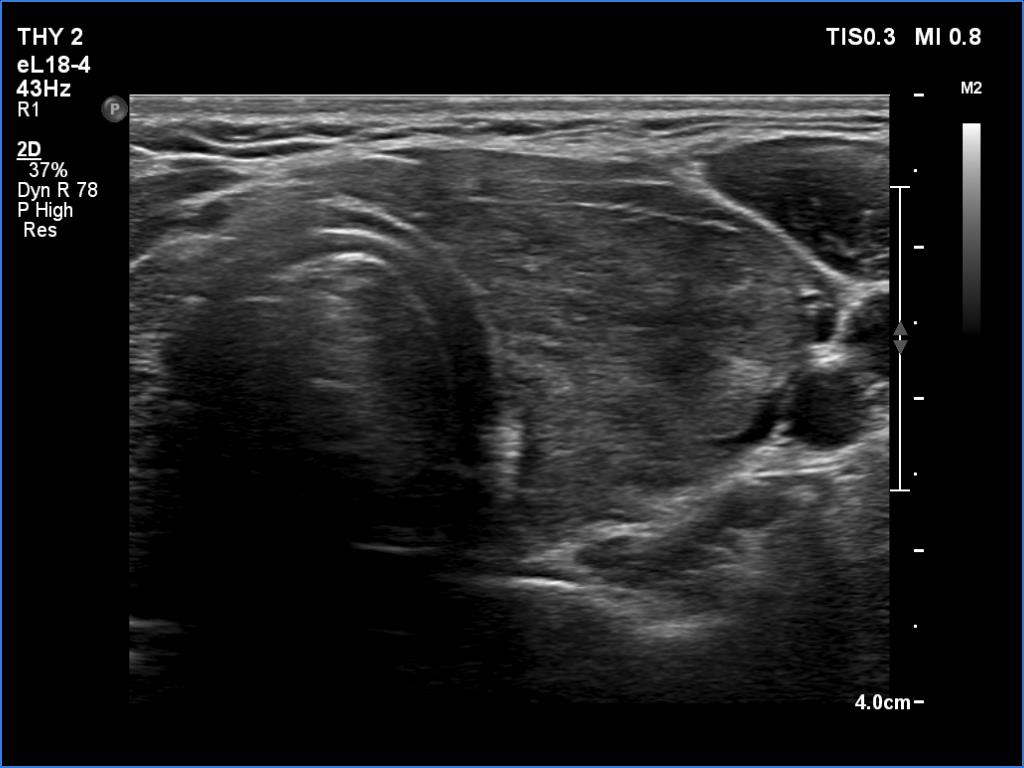

Right lobe, longitudinal scan